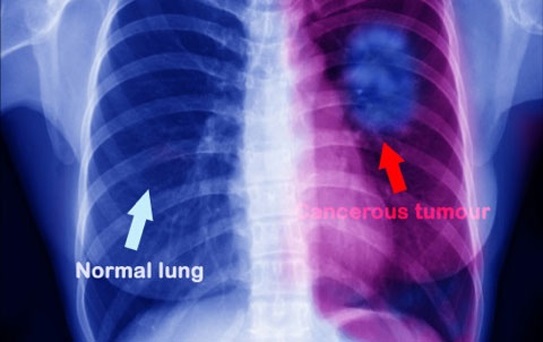

Không nên bỏ qua khi bạn bị đau lưng- Đó là lời khuyên của bác sĩ. Có nhiều người bị đau lưng, đau lưng có thể do ngồi nhiều, lười vận động, nhưng trong một số trường hợp, nó có thể là dấu hiệu ung thư ở phổi. Đây là điều mà những người bị đau lưng phải hết sức lưu ý.

Một người chị họ và dì của Samantha cũng từng bị u não lành tính nên cô nghĩ mình chỉ cần phẫu thuật là mọi chuyện sẽ đâu vào đấy. Nhưng quả thật sét đánh ngang tai khi họ bảo cô bị ung thư phổi giai đoạn IV, và nó đã di căn lên não. Cô bị đau lưng chính là do khối u ở phổi gây ra, và Samantha được kết luận chỉ còn 12-18 tháng để sống.

Chẩn đoán cho thấy cô đã bị ung thư phổi di căn.